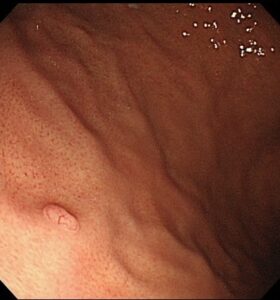

胃底腺ポリープは、周囲の正常な胃粘膜と同じ色調の良性のポリープです。

表面は平滑でツルツルした印象を与えるポリープです。

ヘリコバクター・ピロリ菌に感染していない綺麗な胃粘膜に発生することが多く、胃の胃底腺領域(ひだがある部分)に発生しやすいポリープです。